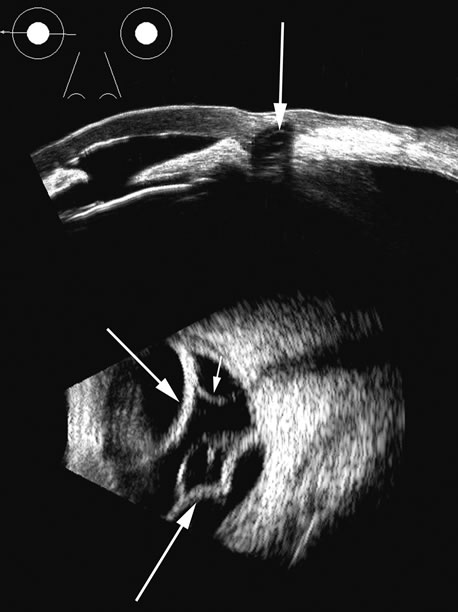

Fig. 17. This patient with a Molteno tube was treated for glaucoma. The top 50 MHz B-scan clearly shows the Molteno Tube (arrow). The bottom 10 MHz B-scan of the same patient demonstrates a choroidal detachment (large arrow) with associated posterior retinal detachment (small arrow). Choroidal elevations are typically convex, highly reflective surfaces with posterior limitation at the vortex vessels. Retina will always attach at the optic nerve. Choroidal elevations are often noted in several quadrants, as seen here.